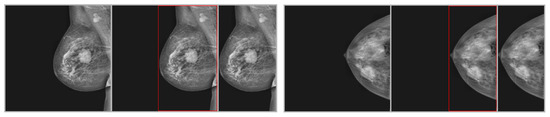

Pixel values were normalized through the z-scoring technique after cropping [44]. Since the number of slices was not constant among the different patients and image types, a nearest-neighbor resampling technique was employed to achieve a consistent 30 slices for each image type and case. Image cropping was performed using Python v3.13.2 and Scikit images v1.1. Though z-scoring and fast nonlocal denoising techniques were executed using Python and OpenCV (version 0.16.1), the complete preprocessing of available images was performed automatically. All images were obtained from the same session and position, so there was no need for co-registration of different sequences for this research. The output of cropping is shown in Figure 4.

Figure 4.

Steps of cropping the ROI for two sample images from the INbreast dataset. The first image is an input image, the second is a detected ROI, and the third is a cropped image.